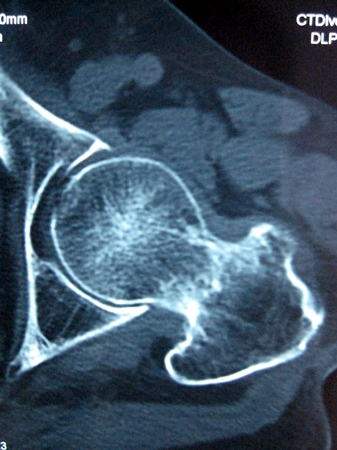

以下是引用lkc8963在2008-12-19 21:19:00的发言:[br]左?右?患侧大转子上移,股骨颈骨质浓杂,髋周见多发条片状骨化影,以小转子为著,多为陈旧性股骨颈骨折后改变并骨化性肌炎.请咨询既往史!